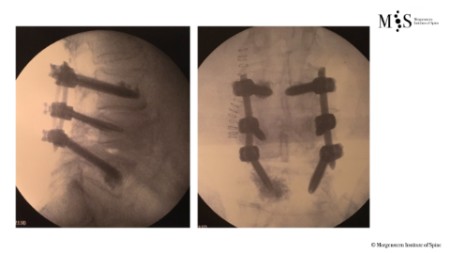

Exemple cas clínic cifoplastia

Comparació pre- i post-operatoria d’una cifopastia cementada

Dona, edat 55 anys, fractura aixafament dret de L2

Abans 1

Després 1

Abans 2

Després 2